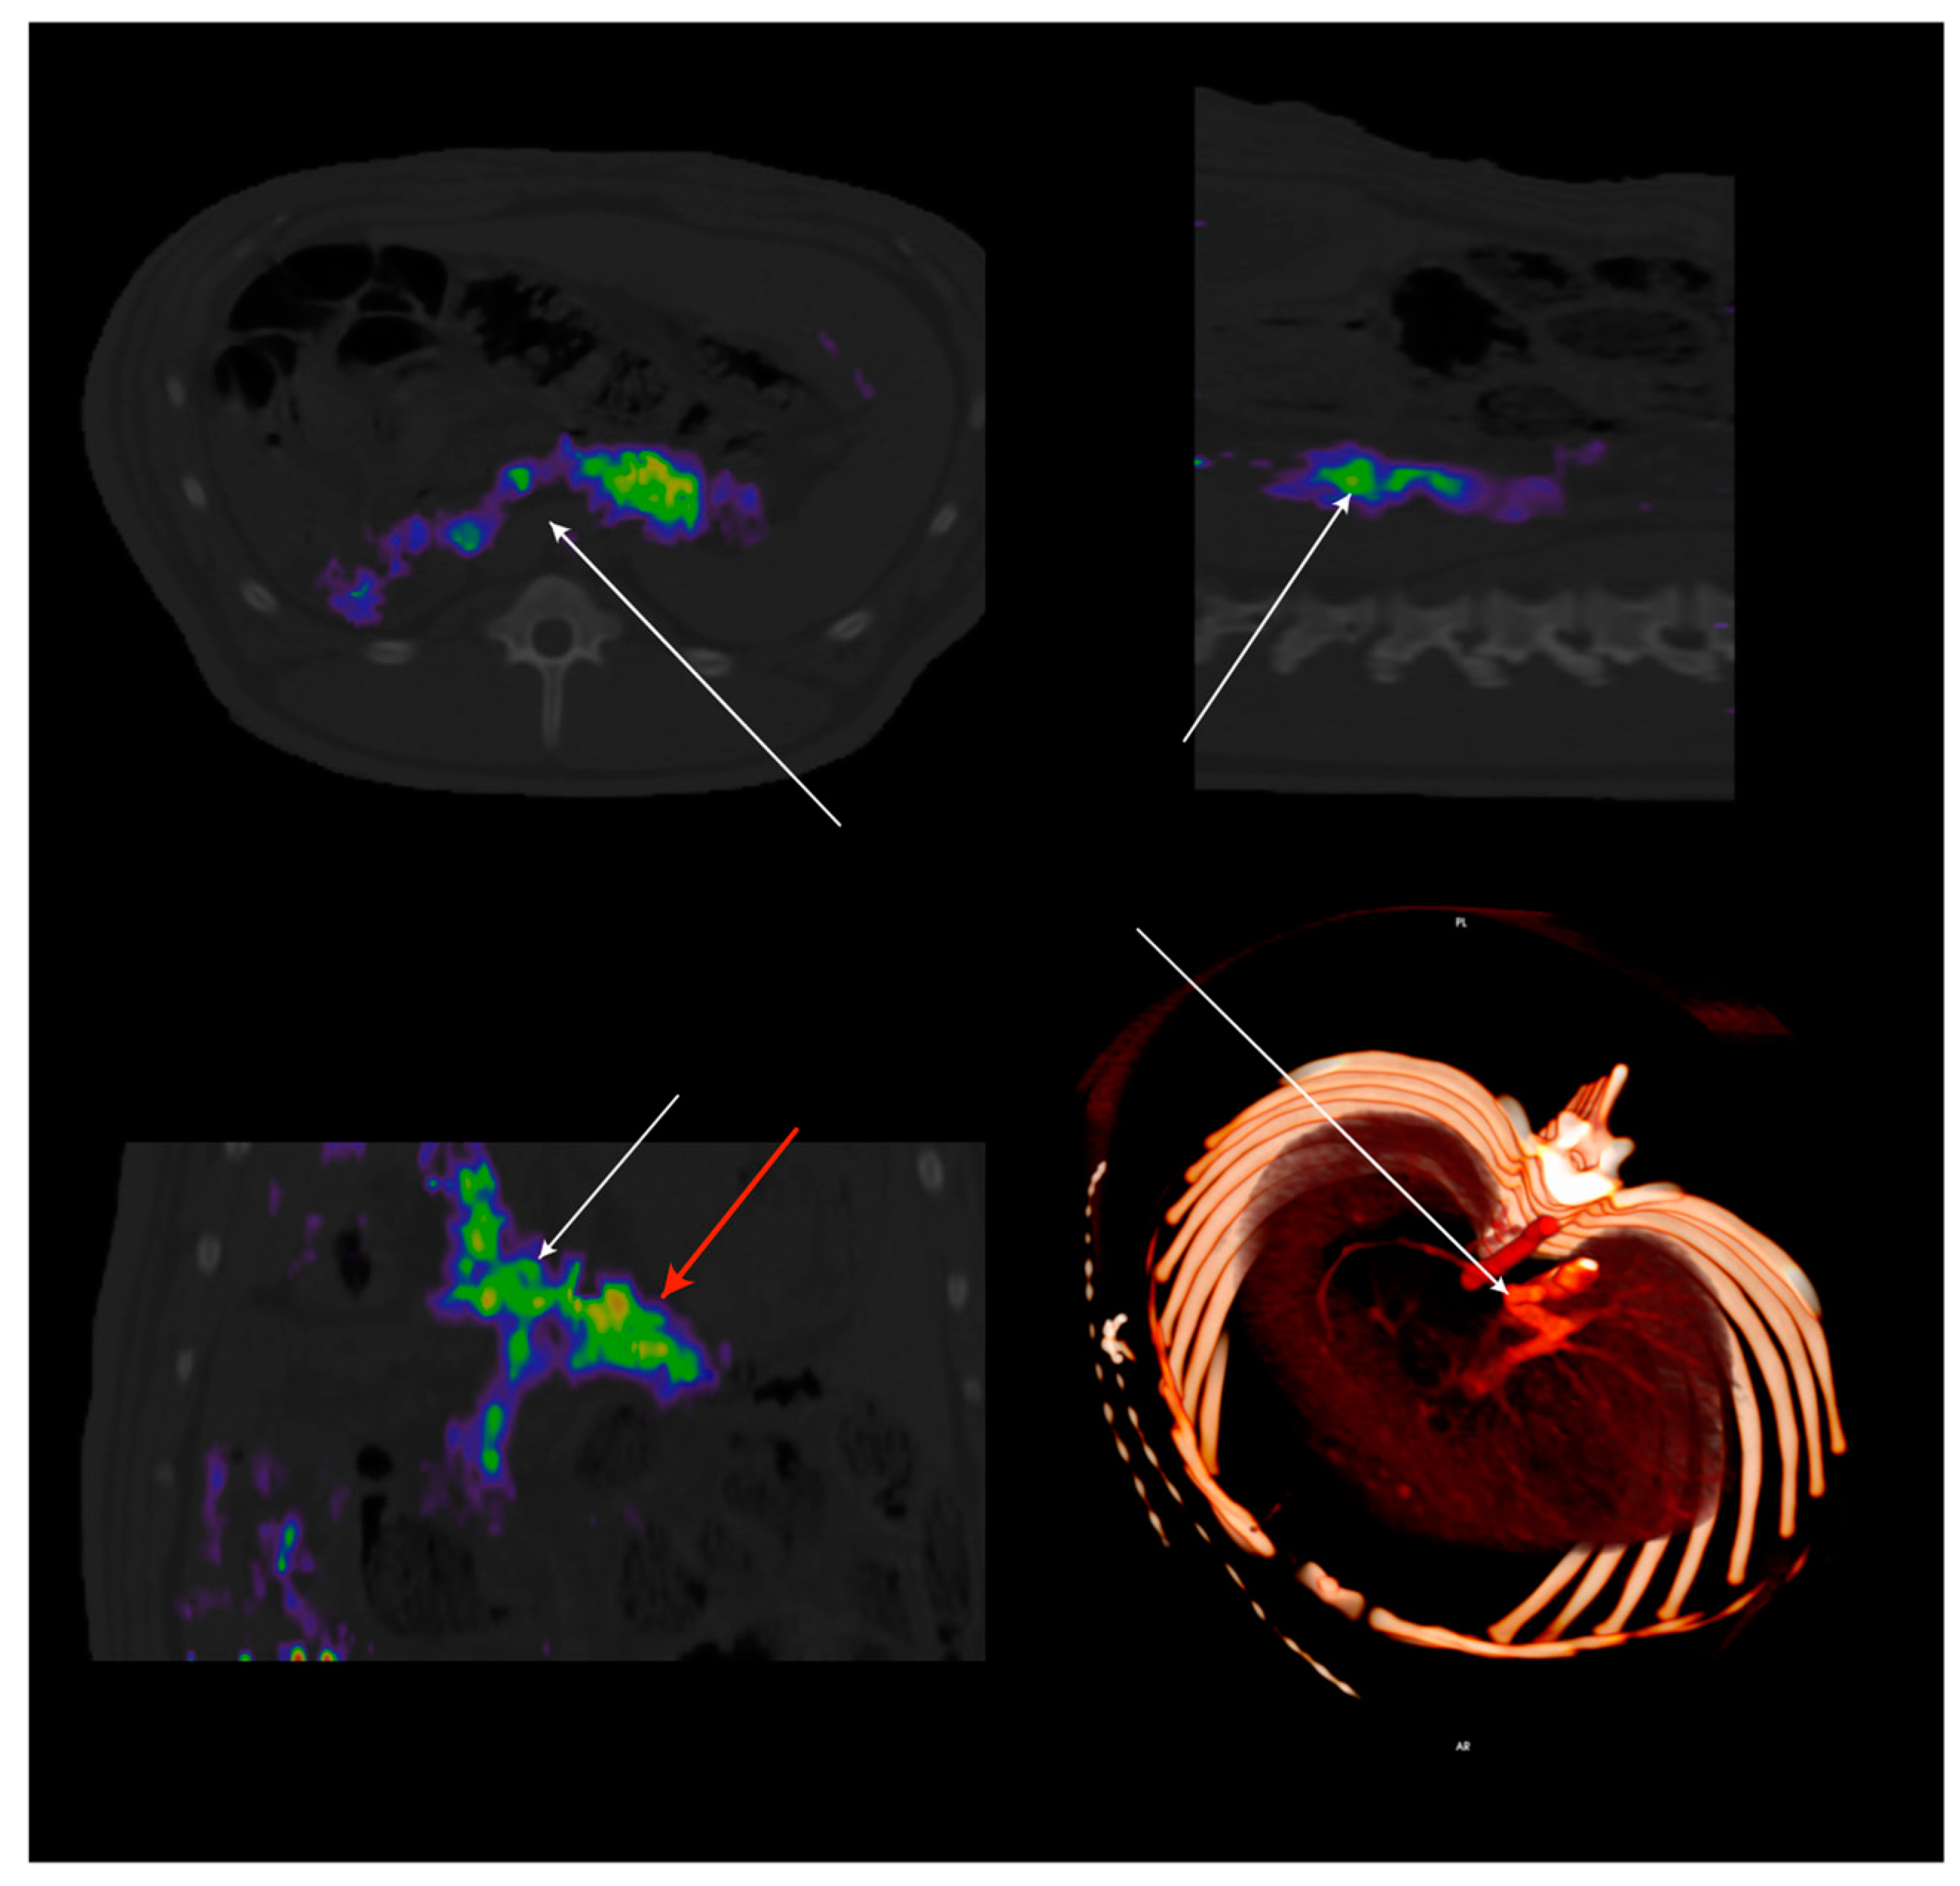

- Malbert, C.-H.; Bobillier, E.; Picq, C.; Divoux, J.-L.; Guiraud, D.; Henry, C. Effects of chronic abdominal vagal stimulation of small-diameter neurons on brain metabolism and food intake. Brain Stimul. 2017, 10, 735–743. [Google Scholar] [CrossRef]

- Malbert, C.-H.; Genissel, M.; Divoux, J.-L.; Henry, C. Chronic abdominal vagus stimulation increased brain metabolic connectivity, reduced striatal dopamine transporter and increased mid-brain serotonin transporter in obese miniature pigs. J. Transl. Med. 2019, 17, 78. [Google Scholar] [CrossRef]